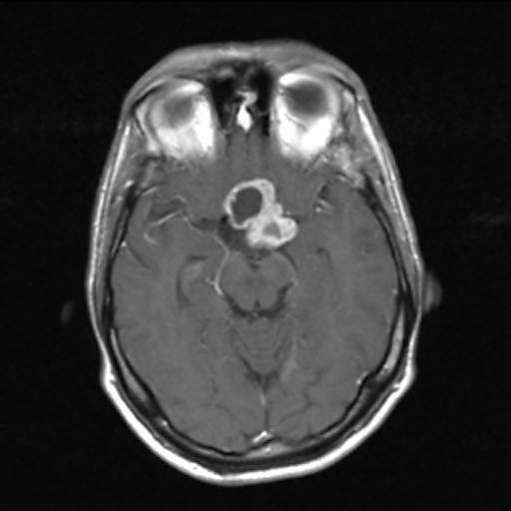

Магнитно-резонансная томография (МРТ) даёт возможность определить точные размеры краниофарингиом, соотношение их узловой и кистозной частей, размеры и локализацию. Также МРТ даёт представление о состоянии желудочковой системы, наличии или отсутствии гидроцефалии, топографо-анатомическом взаимоотношении опухоли и дна III желудочка[32].

Сигнал от данного новообразования вариабелен[35]. В большинстве случаев кистозный компонент имеет гипоинтенсивный сигнал в режиме Т1 и гиперинтенсивный — в режиме Т2. При наличии высокой концентрации белка, продуктов распада крови, холестерина сигнал от кистозной жидкости может существенно меняться[36]. Это проявляется в повышении интенсивности сигнала. Данная особенность является высокоспецифичной именно для краниофарингиом. В режиме Т2 яркость сигнала может варьировать от гипер- до изоинтенсивного[32].

Солидная часть краниофарингиом в большинстве случаев не отличается по интенсивности сигнала от вещества мозга. При введении контрастных препаратов плотность сигнала усиливается[32].

При эндоселлярных краниофарингиомах размеры турецкого седла увеличены. Распространяясь вверх, новообразование заполняет область хиазмальных цистерн, в той или иной степени поддавливает дно III желудочка. Супраселлярная часть краниофарингиом чаще кистозная. Кисты могут распространяться на основание передней черепной ямки, перивентрикулярно или определяться внутри узловой части опухоли. Краниофарингиома чаще всего хорошо отграничена от прилежащего мозгового вещества[32].